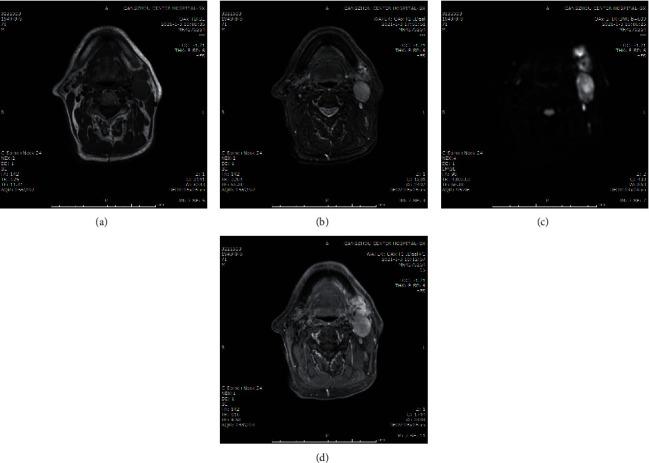

289 patients with HNSCC were divided into lymph node metastasis group (LNM group, = 171) and non-LNM group ( = 118) according to the pathological examination results. MRI was used to scan the patient's lesions and cervical lymph nodes, and ADC was measured by MRI diffusion weighting imaging. The expression of CXCR4 in tumor tissues was detected by qRT-PCR. Logistic regression was used to analyze the risk factors of HNSCC lymph node metastasis. ROC curve was used to analyze the diagnostic effects of MRI, CXCR4, and MRI combined with CXCR4 on HNSCC lymph node metastasis.

Compared with the non-LNM group, patients in the LNM group had a lower degree of pathological differentiation, and the positive rate of TNM staging and vascular invasion was higher. The signal intensity of T1WI and T2WI were low intensity and high intensity, respectively, and the ADC value was significantly reduced. At the same time, the expression level of CXCR4 in the tumor tissues of the LNM group was also significantly increased. In addition, compared with MRI and CXCR4 used alone, MRI combined with CXCR4 has a higher predictive value.